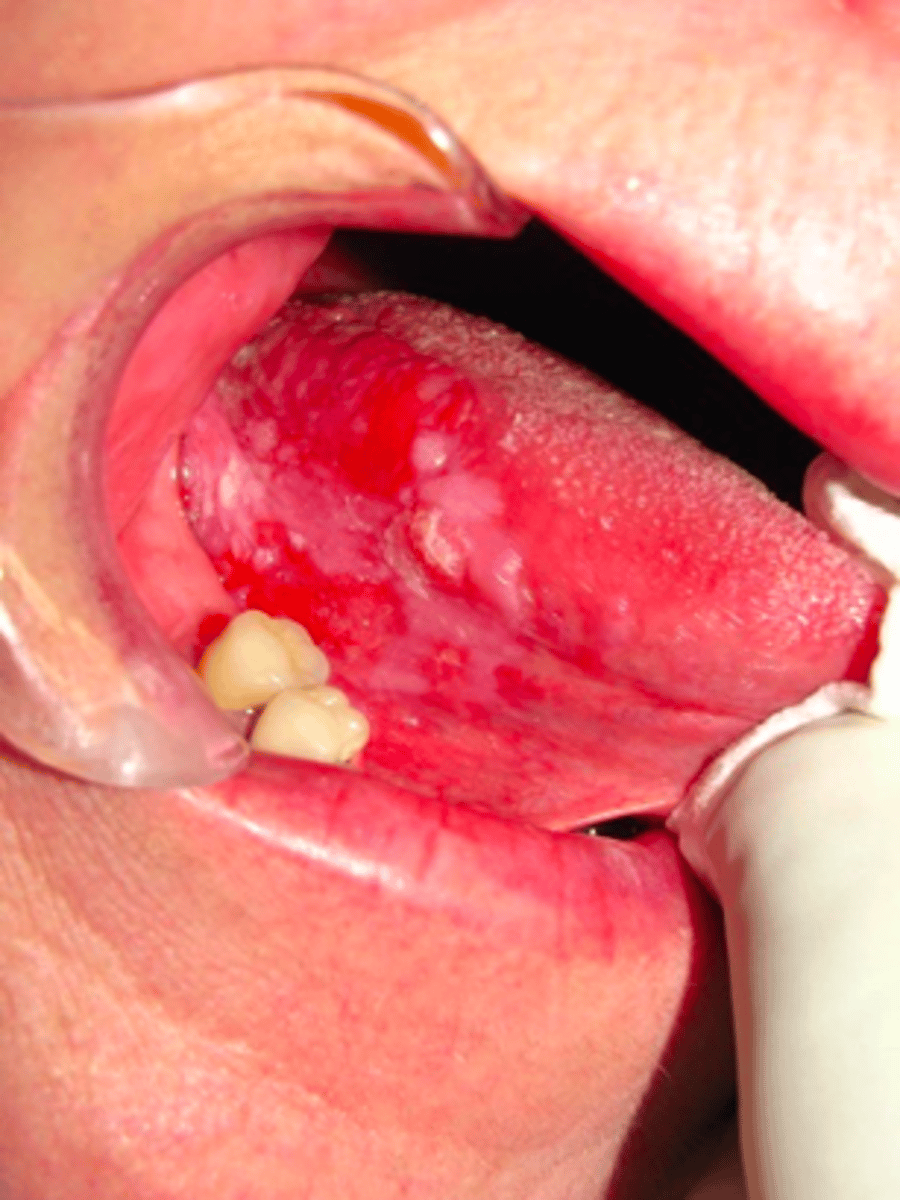

Leukoerythroplakia

What lesion color should raise suspicion of malignancy:

- ulceration persisting more than 2 week

- rapid growth

- bleeding

- indurated/firm

- fixation/immoblie

What lesion characteristics should raise suspicion of malignancy:

- floor of mouth

- ventral lateral tongue

An ulcer in what location of the mouth should raise suspicion for oral malignancy:

Incisional

a patient presents with a non-healing leukoerythroplakic ulcerated lesion on the ventral latereral border of the tongue. The lesion has been there for 3 weeks. What type of biopsy should you take?